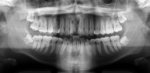

8d0d00fe-27af-4db0-ada6-1fe9359c3ec0.jpeg

Всегда думал, что мне удалили эту восьмерку, а нихуя)

пришел к стоматологу просто посмотреться, в целом сказала, все ок.

Я говорю, у меня вот ряд немного искривился нижней, думаю может из-за правой восьмерки, она говорит сделай ортопанораму, сделал, а там у меня лежачая восьмерка слева(((

Всю жизнь болит шея слева и челюсть хрустит и пятка еще на ноге начала ныть года 2 назад. Эта вся хуйня может из-за него быть?

Куда обратиться лучше, удалить ебучие 8ки?

Аноним 19/07/24 Птн 19:00:47 #18 №1556155

>>1556153

Эта хуйня у тебя под удаление. Мимо стоматолог.